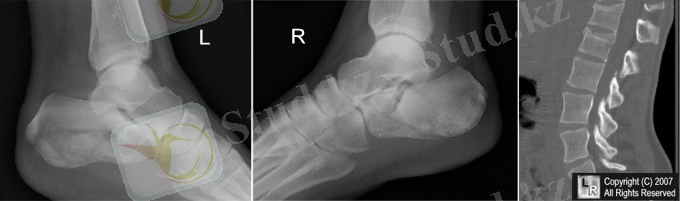

Диагностикасы. Жарақаттан кейінгі ерте кездегі шағымдары зақымдану орнында ауырсыну. Ауырсыну интенсивтілігі науқастың жалпы жағдайына, жұмсақ тіндердің зақымдануына және сүйектің зақымдану ауырлығына байланысты болады. Биіктен құлаған кезде омыртқалардың сынығы табан және тізе- сирақ буындарының сынығымен бірге болады, және аяқтағы ауырсыну өте қатты болады, сондықтан омыртқа зақымдануын анықтау қиынға түседі. Сондықтан ең бірінші анамнезді толық жинап, зақымдану механизмін түсініп, клиникалық тексеруді дұрыс жүргізу керек.

Радиологиялық зерттеулер. Тексеруді көрсеткіш екі проекциялы ретгенннен бастайды, алдыңғы артқы және бүйір, рентгенограмманың ортасында клинасмен анықталған зақымданған ошақ орналасады. Алдынғы артқы проекцияда көлденең өсінділер зақымдануы, омыртқалардың бүйірлык шығулары, ал қалған сынықтар бүйір проекцияда жақсы көрінеді. Әдеттегі сынықтардардың орнын білу кезінде рентгенологиялық тексеру барысында барлық кеуде бел ауысуын (бел омыртқаларының сынығына күдіктенгенде ) және мойын- кеуде ауысуында төменгі мойын омыртқаларының сынығын анықтағанда, науқас қолы төменге қарай, иық және иықүсті буының төмен түсіру арқылы рентген суретін жасаймыз. Рентгенограмманы бағалаған соң, керек жағдайда томограммыа, қиғаш проекциялы рентгенограмма, жасауға болады, Омыртқаның шығуы болатын болса, жоғары орналасқан омыртқа шыққан деп есептеледі. (рис. 5 а, б)

Омыртқа денесінің сынығының рентгендік көрінісі ретінде бүйір проекциядағы сына тәрізді деформация болып табылады. (рис. 5, в) .

Рис. 5. омыртқа зақымлдануы кезінде рентегн зерттеуі.

а -С3 омыртқасының алдыға қарай шығуы, б - С5омыртқасының малдыға шығуы, в - компрессионный перелом II L2 омыртқа денесінің II дәрежелі компрессиялы сынығы